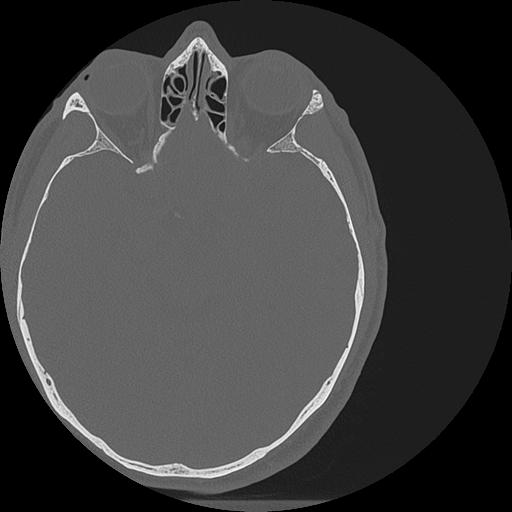

7 HUESO,,Vol,0.5,HUESO,,